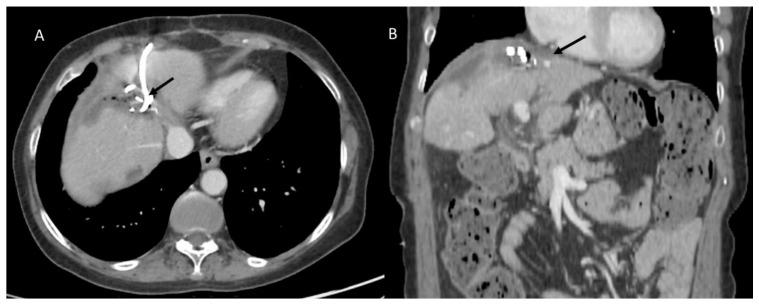

肝切除术后并发症的影像学特征:放射科医生面临的挑战

Imaging Features of Post Main Hepatectomy Complications: The Radiologist Challenging.

In the recent years, the number of liver resections has seen an impressive growth. Usually, hepatic resections remain the treatment of various liver diseases, such as malignant tumors, benign tumors, hydatid disease, and abscesses. Despite technical advancements and tremendous experience in the field of liver resection of specialized centers, there are moderately high rates of postoperative morbidity and mortality, especially in high-risk and older patient populations. Although ultrasonography is usually the first-line imaging examination for postoperative complications, Computed Tomography (CT) is the imaging tool of choice in emergency settings due to its capability to assess the whole body in a few seconds and detect all possible complications. Magnetic resonance cholangiopancreatography (MRCP) is the imaging modality of choice for delineating early postoperative bile duct injuries and ischemic cholangitis that may arise in the late postoperative phase. Moreover, both MDCT and MRCP can precisely detect tumor recurrence. Consequently, radiologists should have knowledge of these surgical procedures for better comprehension of postoperative changes and recognition of the radiological features of various postoperative complications.

近年来,肝切除术的数量有了显著增长。通常,肝切除术仍是治疗各种肝脏疾病的方法,如恶性肿瘤、良性肿瘤、包虫病和脓肿。尽管在专业中心的肝切除领域有技术进步和丰富经验,但术后发病率和死亡率仍处于中等偏高水平,尤其是在高危和老年患者群体中。虽然超声检查通常是术后并发症的一线影像学检查,但计算机断层扫描(CT)因其能够在几秒钟内评估全身并检测所有可能的并发症,所以在紧急情况下是首选的成像工具。磁共振胆胰管造影(MRCP)是用于描绘术后早期胆管损伤和术后晚期可能出现的缺血性胆管炎的首选成像方式。此外,多层螺旋CT(MDCT)和MRCP都能精确检测肿瘤复发。因此,放射科医生应该了解这些手术过程,以便更好地理解术后变化并识别各种术后并发症的放射学特征。